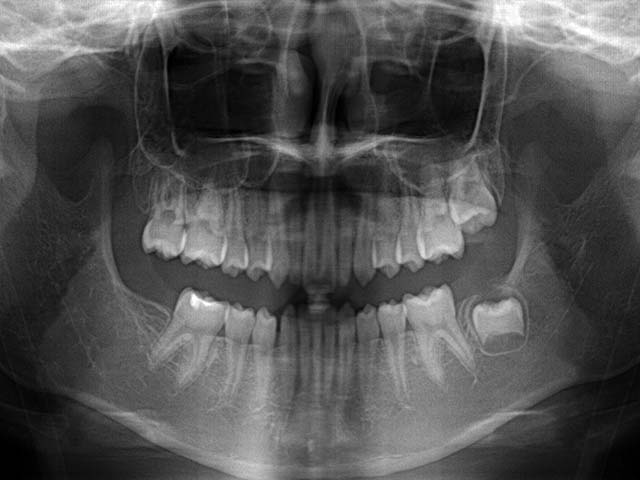

除此之外,兒童拍攝全口X光片還早期發現一些罕見疾病或先天缺牙如下:

1.左下先天性囊腫及缺牙

2.左下及正中門牙先天缺牙

3.右下先天缺牙第二大臼齒